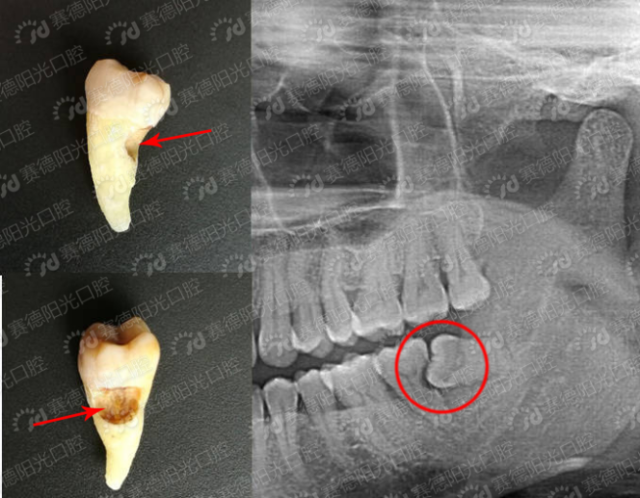

导语:智齿在医学上称为第三恒磨牙(简称第三恒磨牙).

6,第三恒磨牙(智齿)的萌出

(邻牙向缺牙处倾斜,导致缺隙处恒牙萌出受阻) 4,如果第三恒磨牙(智齿)